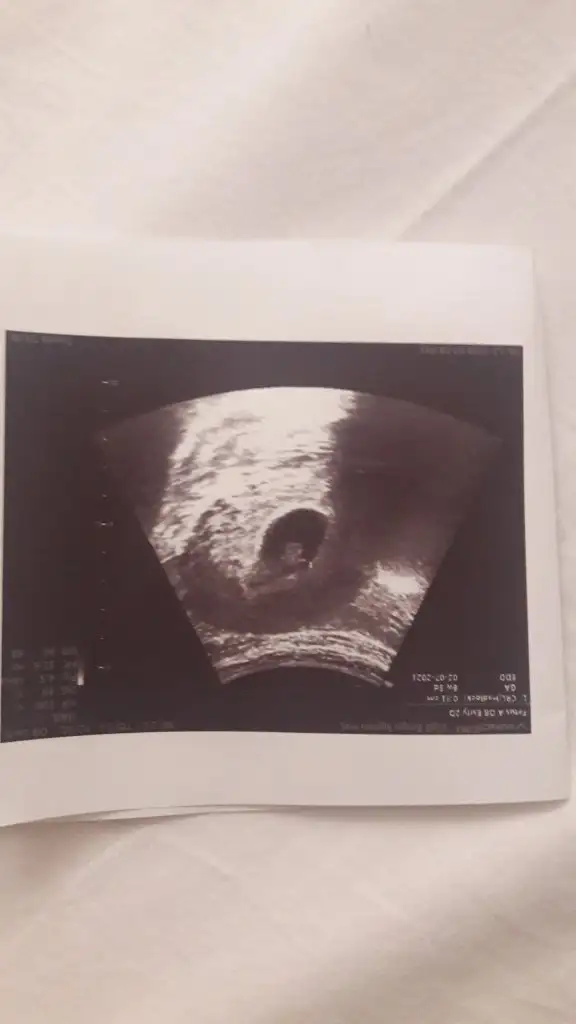

Erkek karından bakıldıysaIkra meyra 6+4 usg yorumlarmısınız kese armut gibiydi ekranda daha net gördüm.

Evet karından bakıldı bidahaki kontrollerde yine atarimErkek karından bakıldıysa